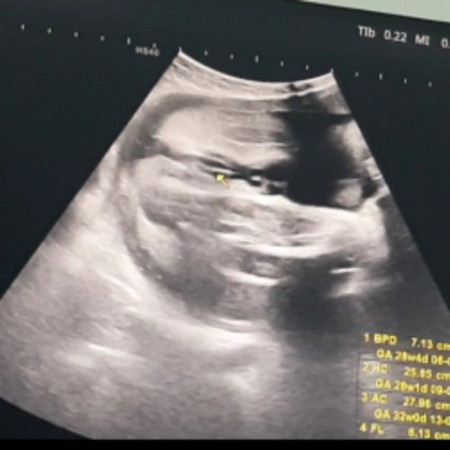

หญิงไหมคะแบบนี้...32wท้องเเรก อยากได้หญิง😁😁😘😘 ขอดูผลซาวด์ของแม่ๆหน่อยจ้า #ขอบคุณล่วงหน้านะคะ